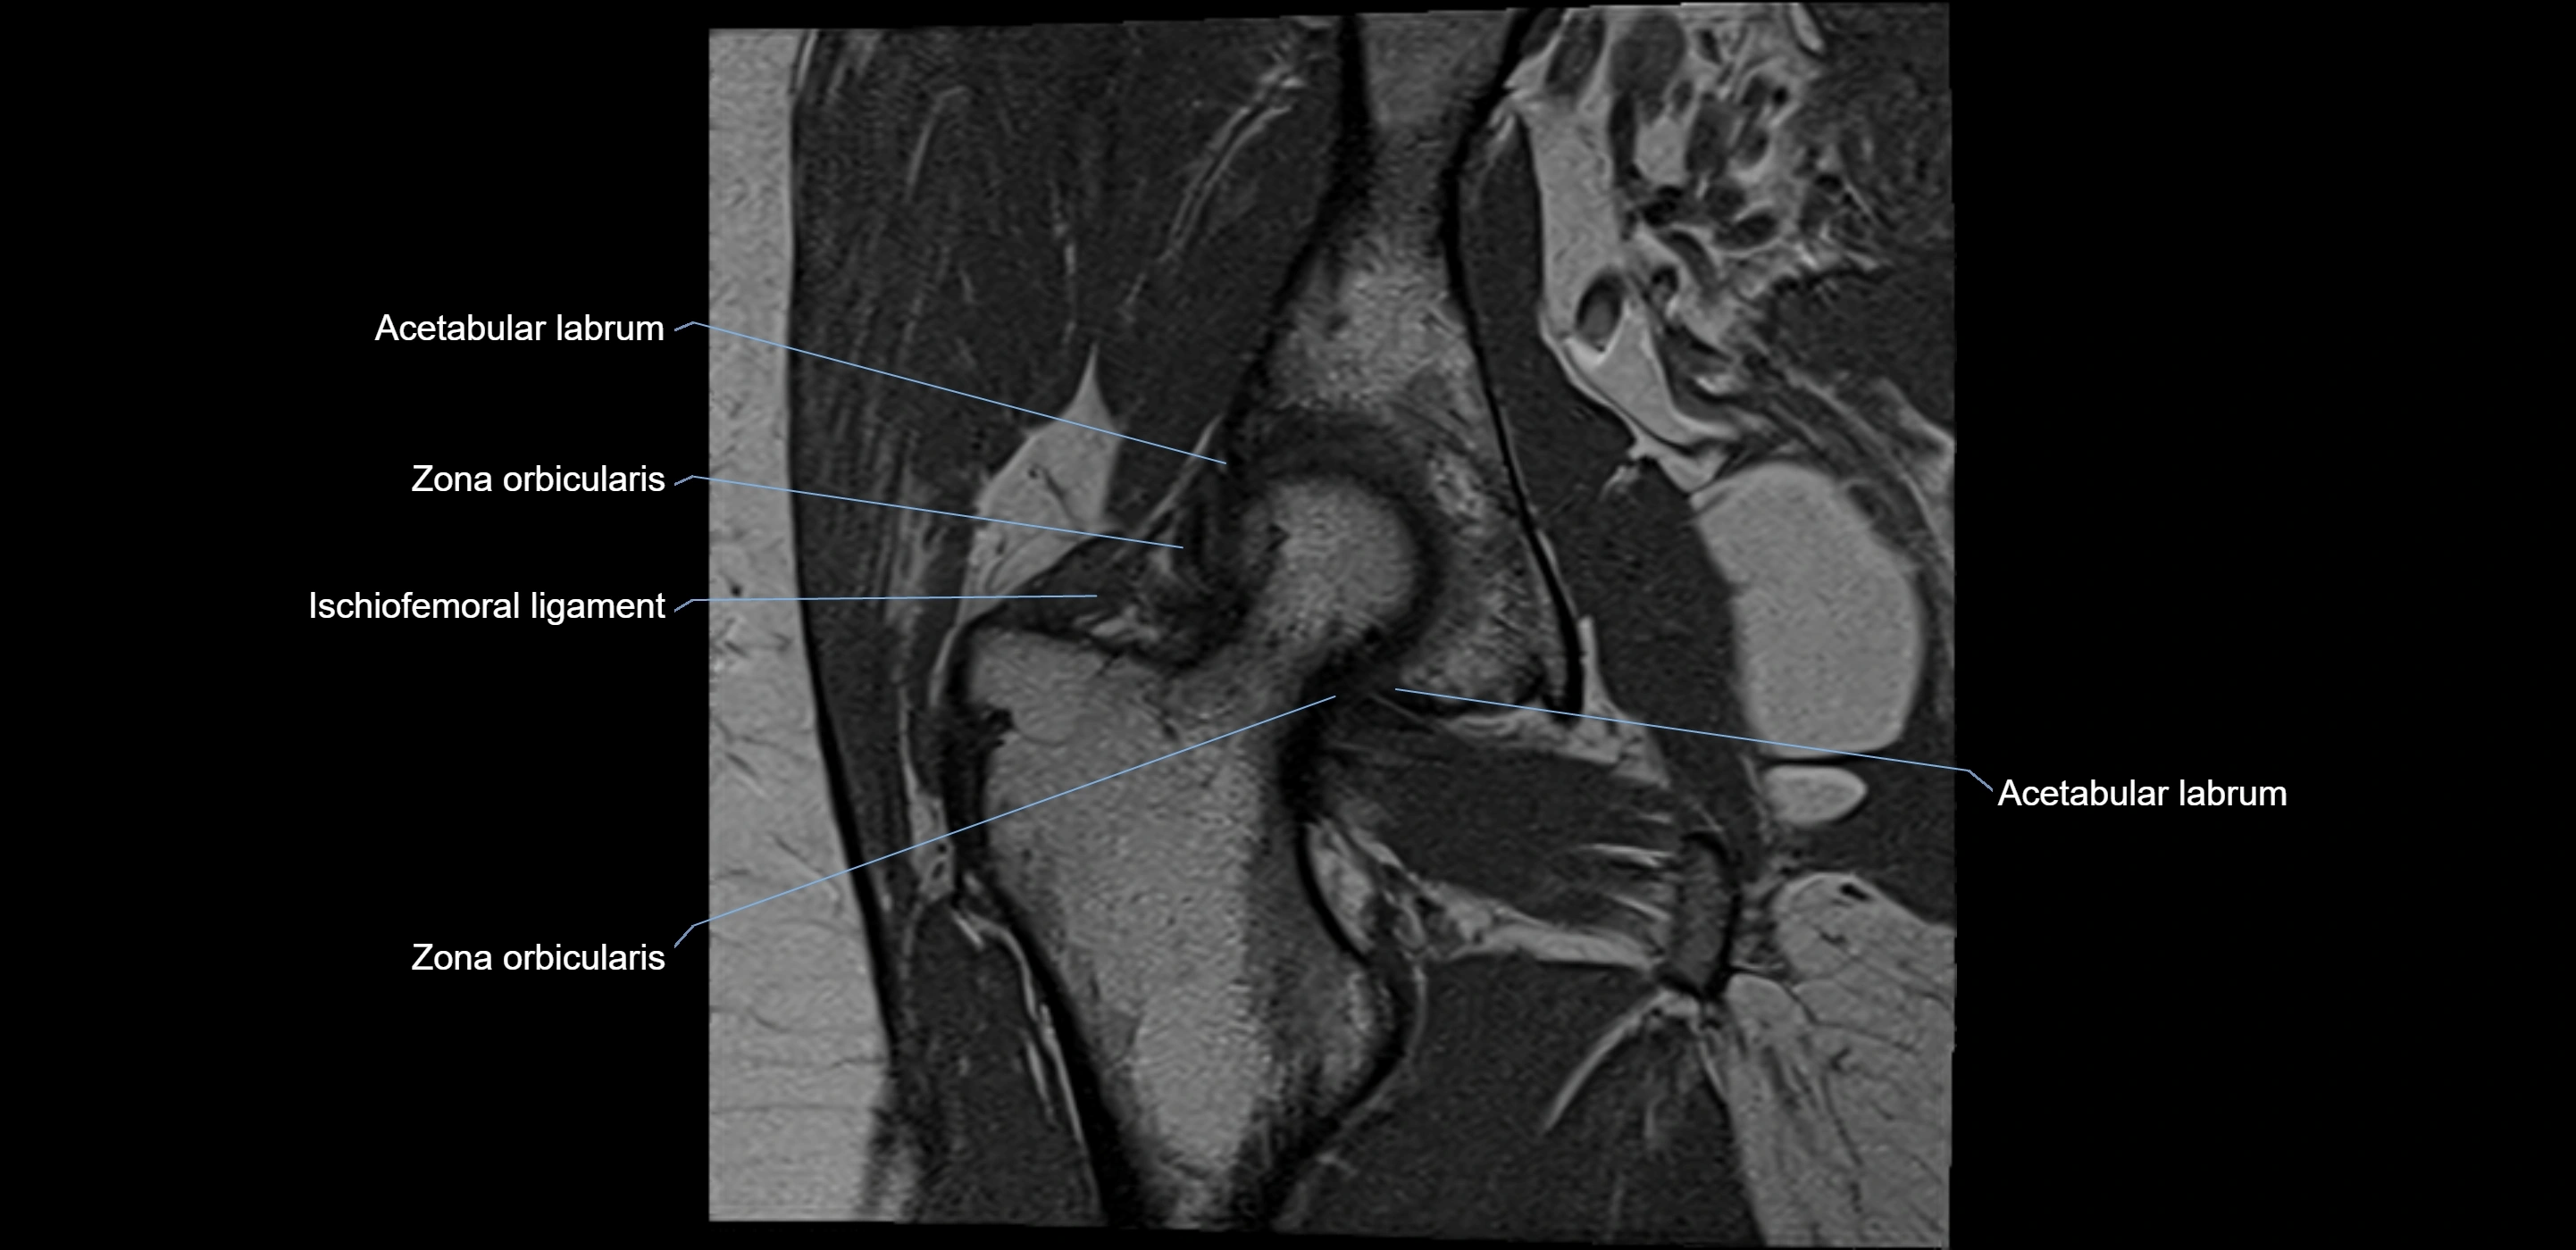

MRI Appearance

T1-weighted images:

• Labrum: low signal intensity (dark)

• Surrounded by intermediate signal joint fluid (bright on arthrogram)

• Tears: linear or focal areas of intermediate-to-high signal interrupting labral continuity

T2-weighted images:

• Joint fluid: bright, making labral tears visible as fluid extending into or around labrum

• Degeneration: may show areas of increased signal within labrum

MRI image

image